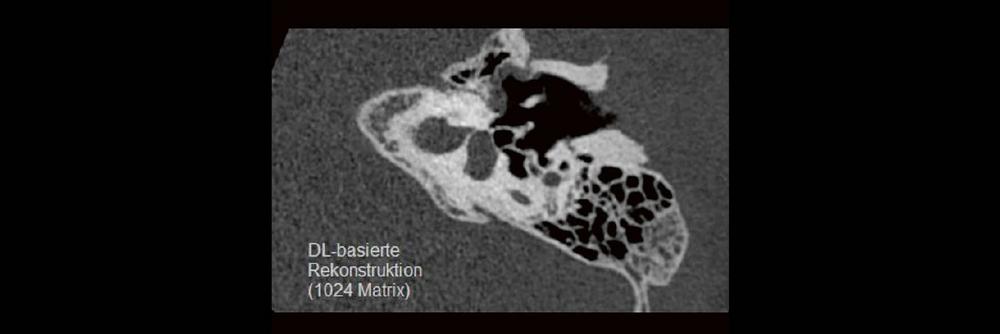

DEEP-LEARNING-REKONSTRUKTION IN DER NEURORADIOLOGIE

Die CT ist ein essentielles Routine-Verfahren in der Neuroradiologie. Bei steigender Bildqualität konnte die Röntgendosis mit neuen Technologien in der letzten Dekade deutlich gesenkt werden, was für die zielgerichtete und möglichst schonende Behandlung von Patienten von großer Bedeutung ist. Mit der Deep-Learning-Rekonstruktion steht ein neues Verfahren zur Verfügung, welches die Befunderhebung noch einmal deutlich verbessert. Technische Hintergründe und klinische Anwendungen im Rahmen der Neuroradiologie werden vorgestellt und diskutiert.